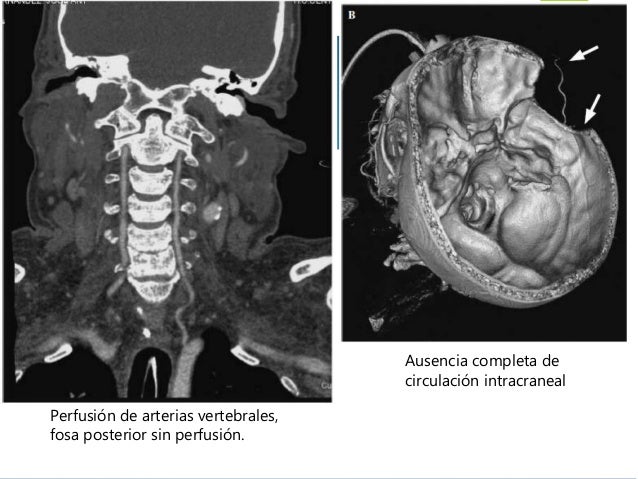

Diagnóstico de la muerte encefálica

Diagnóstico de la muerte encefálica from image.slidesharecdn.com